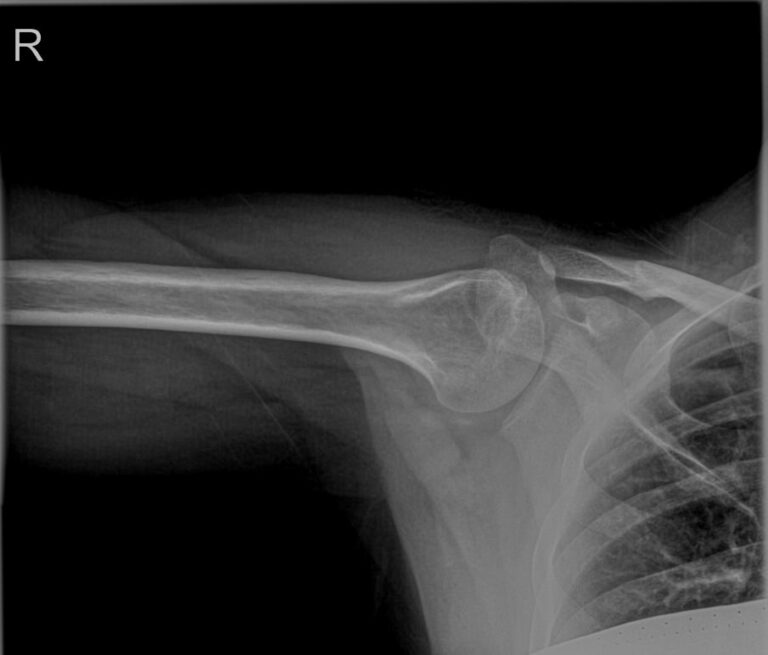

Плечевая кость ― одна из самых крепких в организме, что для ее повреждения требуется удар значительной силы. Переломы могут сопровождаться вывихами плечевого и локтевого суставов. Давно залеченная травма при неблагоприятных обстоятельствах может вызвать прерождение костной ткани.

Во всех случаях первичным методом диагностики будет рентгенография. Это простая и информативная процедура, которая не добавляет неприятных ощущений и быстро показывает полную картину патологии. Современное оборудование, которое используется в клинике «Доступная медицина», позволяет делать несколько снимков в течение короткого времени без опасности чрезмерного облучения.

Что покажет рентген плечевой кости

• Травматические повреждения, в том числе зажившие;

• Формирование костной мозоли;

• Патологические изменения костной ткани: разрежение, некроз, деструкция и другие;

• Состояние смежных суставов, вошедших в снимок;

• Опухоли и метастазы.